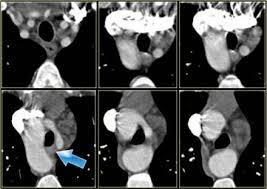

What is the anomaly

Right aortic arch (pushing trachea to the L)

With large posterior diverticulum of Kommerell (post to trachea and esophagus)

Diverticulum gives rise to stenotic L subclavian artery